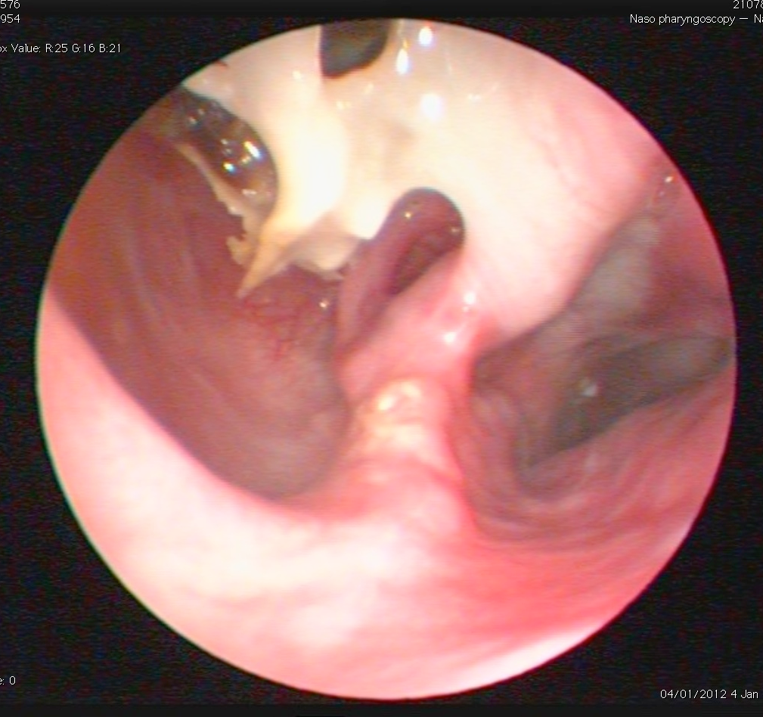

What is the problem here?

See the destruction of the nasal cavity

Blind biopsy may help when you can see there is destruction

What is this? Where is it commonly found/how would we find it?

Nasal FB

Must check the internal nares too!

Retroflex and behind the soft palate